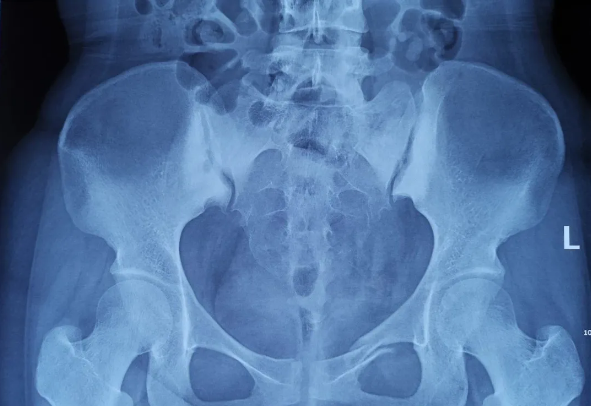

由北京積水潭醫(yī)院院長蔣協(xié)遠、智能骨科研究型病房主任王軍強帶領(lǐng)的智能骨科團隊,運用骨科機器人輔助經(jīng)皮骨盆通道螺釘置入技術(shù),成功救治了一名90歲高齡的骨盆骨折患者。 -

近日,天璣?骨科手術(shù)機器人落戶南昌市第一醫(yī)院,助力骨盆骨折閉合復(fù)位內(nèi)固定術(shù)順利完成。作為江西省首先采用5G引導(dǎo)下的骨科機器人手術(shù),天璣?骨科手術(shù)機器人用它的“透視眼”,以三維影像掃描進行深層三維空間精準定位,為患者“量身定做”了最理想、最安全的教科書般通道,完成了復(fù)雜骨盆骨折微創(chuàng)治療一次性完美置釘及腰椎骨折微創(chuàng)經(jīng)皮置釘?shù)氖仔悖蔀榻魇」强瓢l(fā)展的標志性事件,同時也是江西省骨科步入新型數(shù)字智慧骨科時代的重要里程碑事件。 -